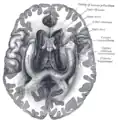

![]() Base of brain (Tuber cinereum visible at center). | |

The tuber cinereum is the portion of hypothalamus[1] forming the floor of the third ventricle situated between the optic chiasm, and the mammillary bodies.[2] The tuberal region is one of the three regions of the hypothalamus, the other two being the chiasmatic region and the mamillary region.[1]

The tuber cinereum is situated caudal to the optic chiasm, medial to the optic tract (which flanks it on either side), and rostral to the two mammillary bodies.[4] is continuous anteriorly with the lamina terminalis, and laterally with the anterior perforated substances.